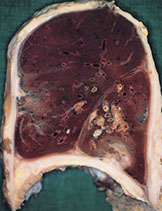

Emphysema - note the bullae and blebs, anthracosis, and that the lungs almost meet in the midline